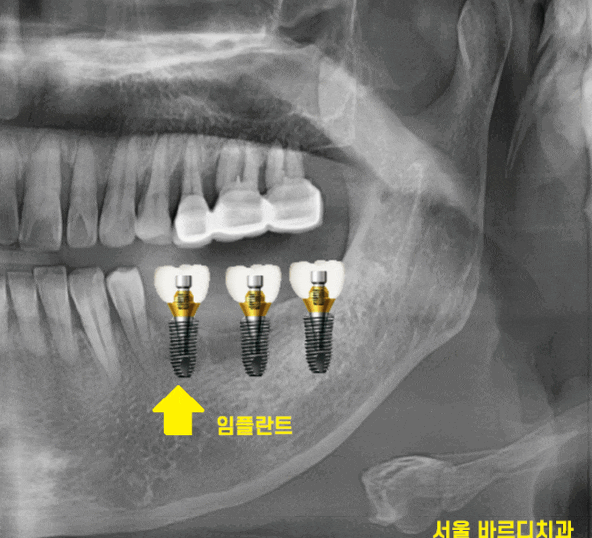

230921

상일동역 치과 수술 직후의 사진입니다.

사진을 보시면 나사가 하나 들어간 것을

확인하실 수 있는데요.

221123

때문에 임플란트 수술을 하고 나면

머리 대신에 작은 나사만 연결해둡니다.

뼈가 거의 없는 경우에는

임플란트를 잇몸 안에 묻어두기도 하는데요.

이럴 경우에는 잇몸밖에 안느껴지기 때문에

임플란트 심은게 맞나.. 싶기도 합니다.

230707

겉으로 봤을 때는 잇몸만 느껴지지만

x-ray를 보실까요~?

230717

임플란트가 잘 심어져있습니다.